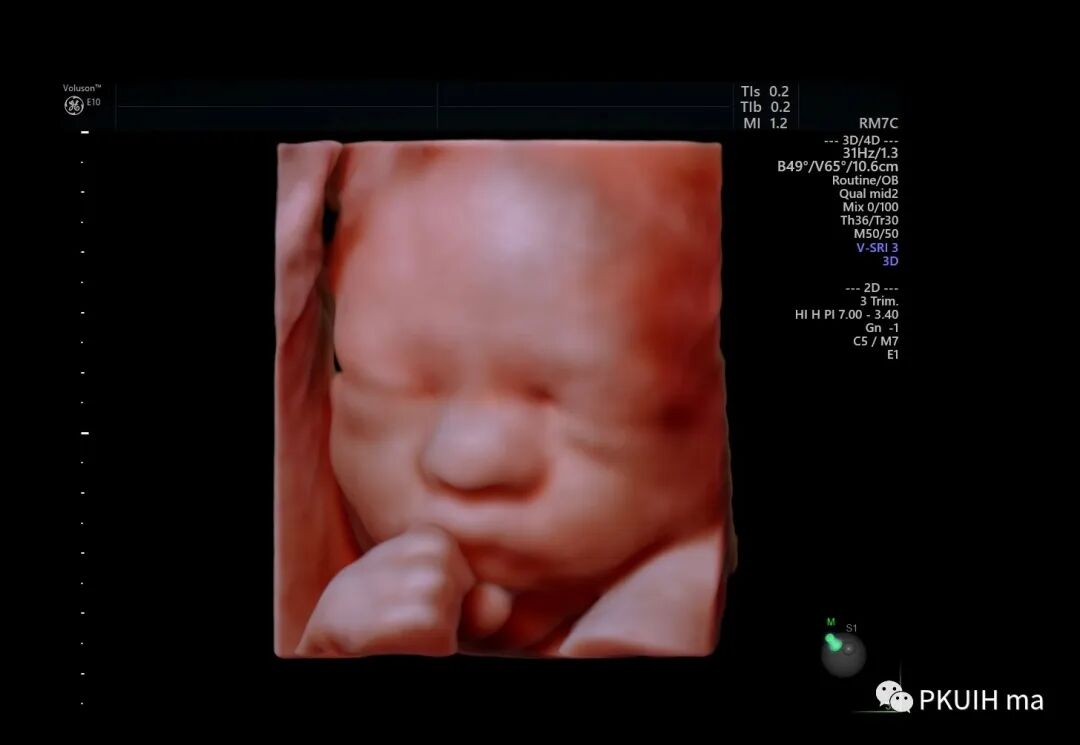

小宝宝在打哈欠

在想美事

在思考或者是安静的休息